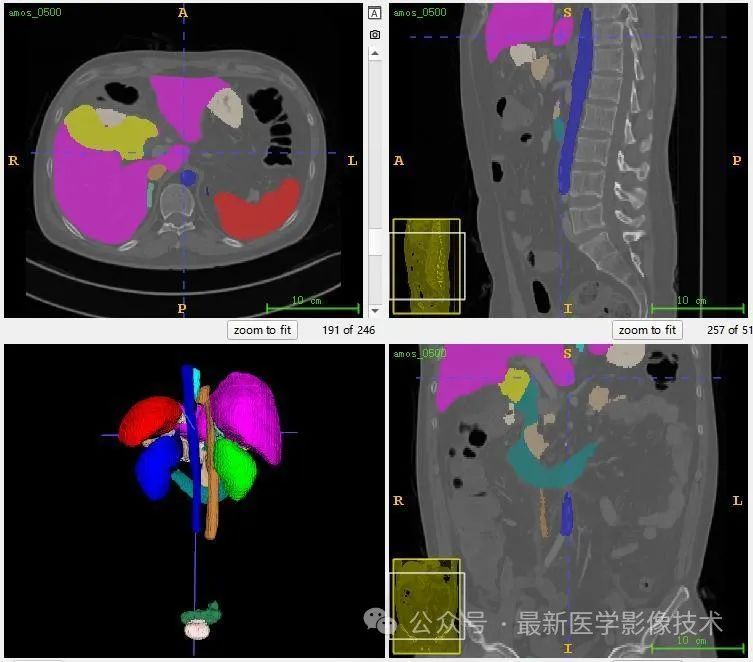

AMOS2022数据集示例说明,提供了 500 例 CT 和 100 例MRI 以及 15 个腹部器官的体素级别注释, 包括脾脏、右肾、左肾、胆囊、食道、肝脏、胃、主动脉、下腹部腔静脉、胰腺、右肾上腺、左肾上腺、十二指肠、膀胱、前列腺/子宫。请注意,某些数据点由于生理移除或由于未扫描身体部位而丢失了某些器官。

共500张CT和MRI,标注了15个器官(脾、右肾、左肾、胆囊、食道、肝、胃、主动脉、下腔静脉、胰腺、右肾上腺、左肾上腺、十二指肠、膀胱、前列腺) /子宫)呈现。请注意,某些数据点由于生理移除或由于未扫描身体部位而丢失了某些器官。

13、测试集分割结果